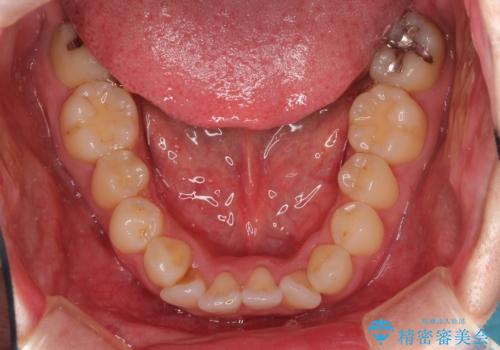

フルリンガル矯正 非抜歯でガタつきを整える

- 30代男性

- 1年6ヶ月

- フルリンガルワイヤーによる非抜歯治療を計画しました。